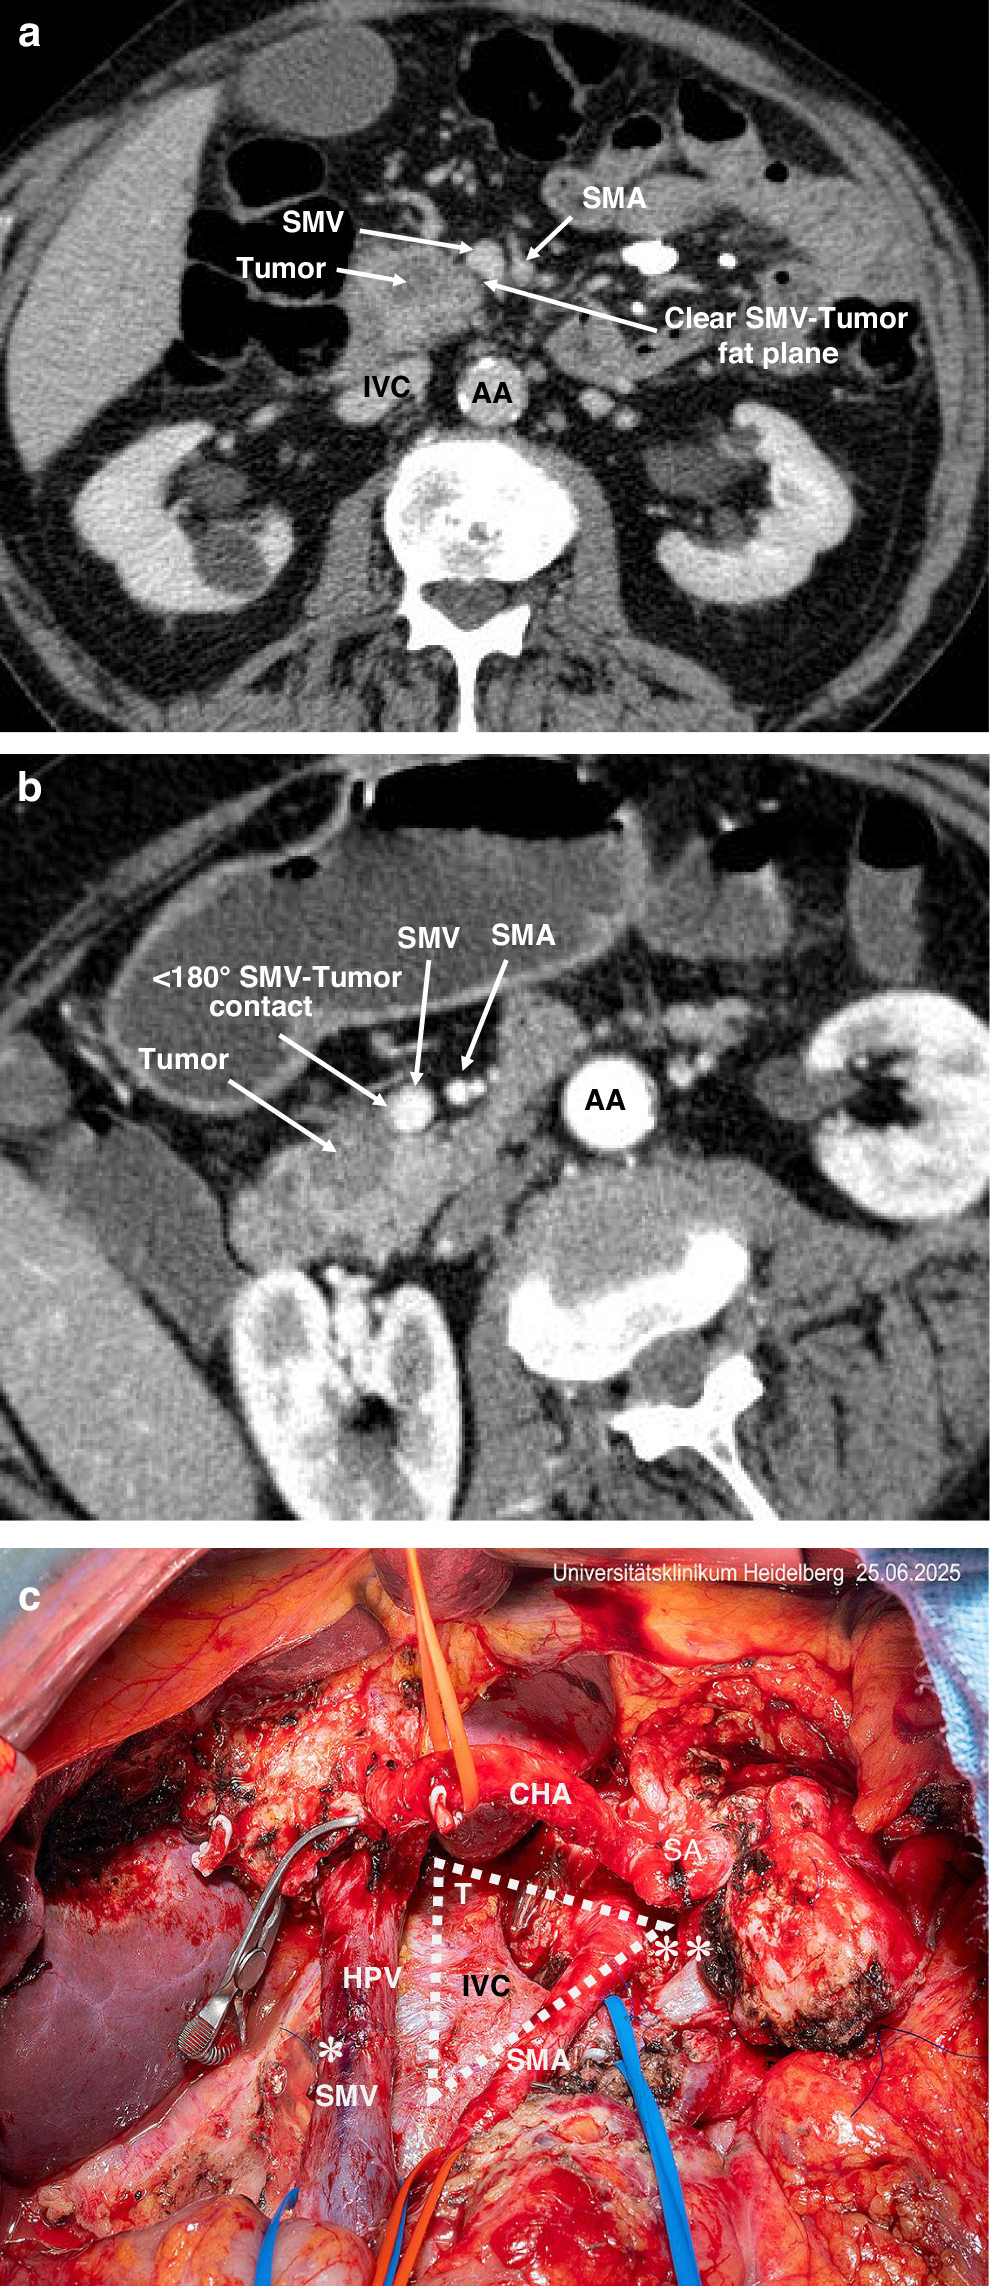

Fig. 1: Preoperative co-axial imaging by CT demonstrating the distinction between resectbale (EmR) and borderline (EmBR) PDAC, and the key features of the TRIANGLE operation.

a CT image of resectable cancer in the head of the pancreas. b CT image of borderline resectable cancer in the head of the pancreas. c Surgical site after partial pancreato-duodenectomy with venous resection, triangle dissection and splenorenal shunt for borderline rectable disease following induction chemotherapy disease. AA abdominal aorta, CHA common hepatic artery, SMA superior mesenteric artery, HPV hepatic portal vein, SMV superior mesenteric vein, SA splenic artery, IVC inferior vena cava, * hepatic portal vein resection, ** splenorenal shunt, T triangle.